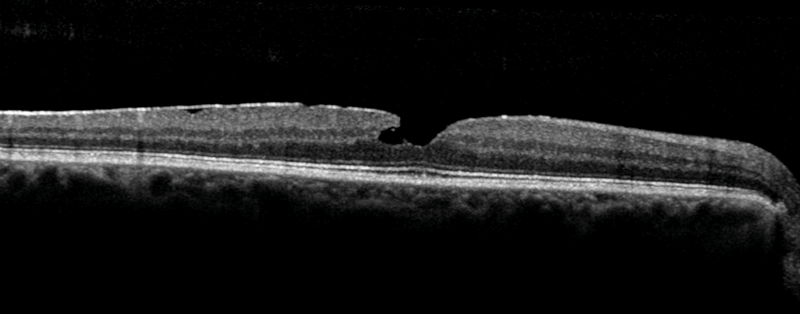

Figure 2: OCT image of a macular hole.

OCT moved rapidly from the research lab to being an essential part of the medical retina clinic. In most cases it replaced the time- consuming and invasive retinal angiography techniques to noninvasive in vivo imaging completed in a matter of seconds. OCT increased capacity, sped up treatment pathways and avoided the side-effects from intravenous injection for our patients, and while angiography is still necessary in some cases, many patients benefit from OCT based diagnostics. Over the last 25 years the technology has dramatically improved the resolution of the retinal images. The images OCT provides can be viewed in two or three dimensions. In response, ophthalmologists had to develop their understanding and interpretation of these images in the context of a rapidly developing area of retinal therapeutics. The availability of OCT expanded the capabilities of our retinal imaging departments and provided a cadre of healthcare professionals with training, accreditation and career pathway. Having OCT and the trained workforce allowed us to set up virtual clinics and explore the benefits of telemedicine.